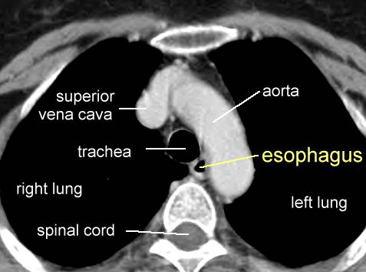

Look and learn this Abdo CT so you’re a good Doctor who understands things :)